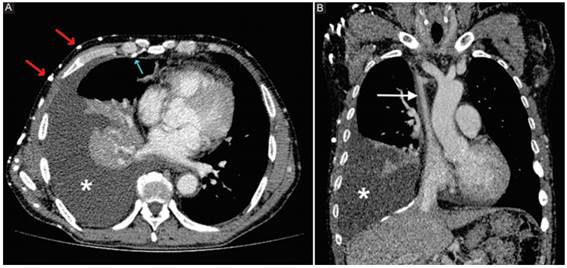

Es útil la visualización de las venas colaterales generadas en otros sectores, así como la comunicación existente entre el sistema de drenaje venoso superior y el sistema porta, a fin de descartar otras posibilidades diferentes a una obstrucción de la VCS (Fig. 3).